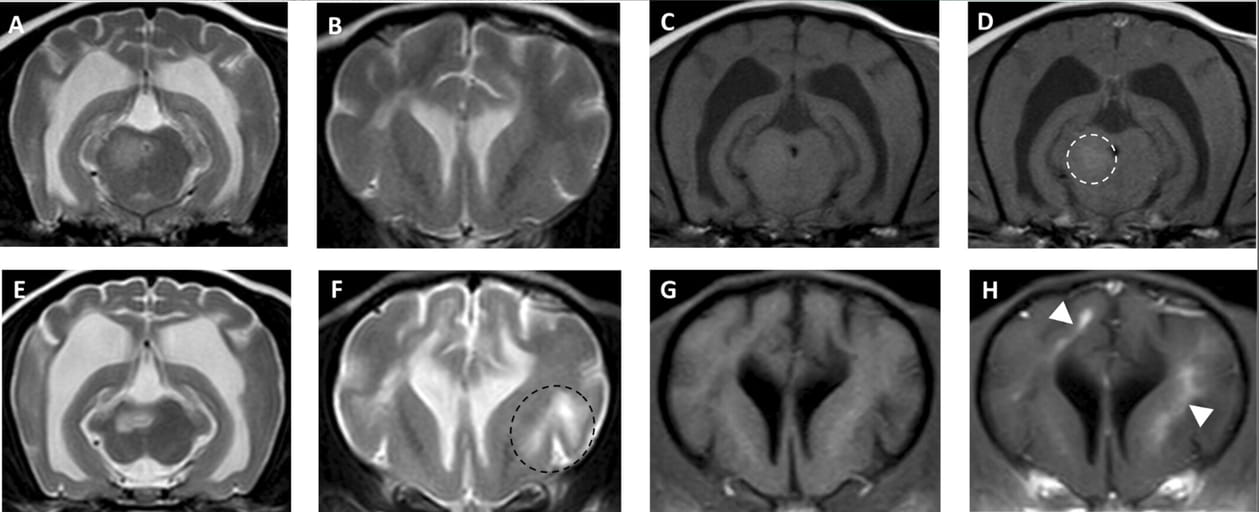

Magnetic resonance imaging of a 3-year-old crossbreed with MUO that showed clinical improvement but remained with permanent neurological deficits at the time of initial diagnosis of MUO (A–D) and 12-months later (E–F). Images (A–B) and (E–F) are transverse T2-weighted (T2W) images, showing enlargement of the lateral ventricles and sulci, suggesting parenchymal atrophy and also development of a new lesion in the frontal cortex (black dotted circle) not seen in the initial MRI. Images (C) and (G) are transverse T1-weighted (T1W) images and (D) and (H) are transverse T1W post-contrast images showing the only mildly contrast enhancing lesion in the initial MRI (dotted white circle) and the new areas of contrast enhancement in the second MRI (white arrowheads).